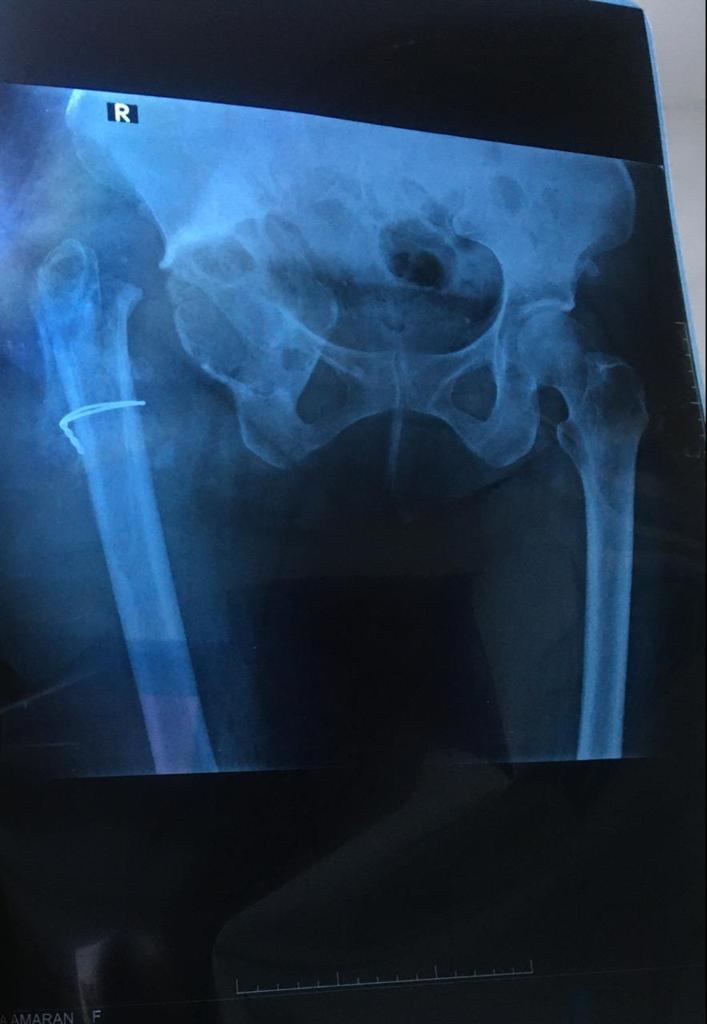

Revision Total Hip Arthroplasty